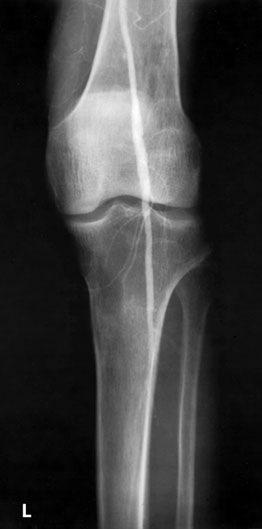

This patient developed several strictures two years apart. This one is a popliteal stricture.

Popliteal stricture post dilatation

And this represents the second stricture two years later in the left lower femoral artery

And this is the post-dilatation image of the femoral stricture.